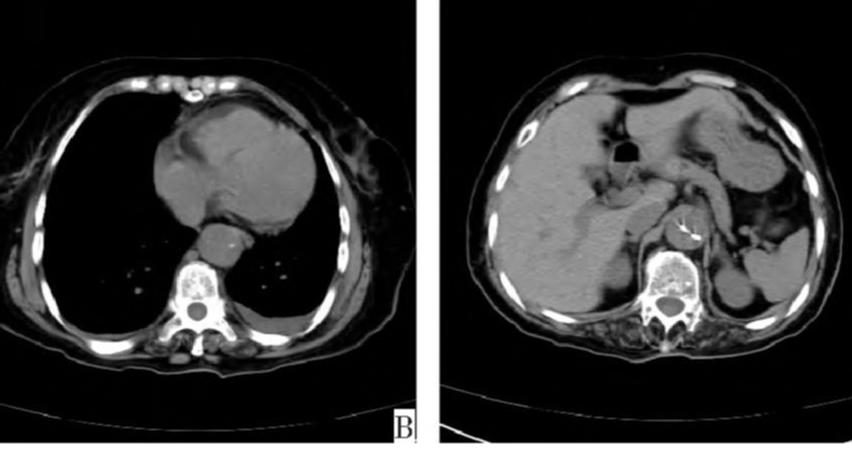

下图的胸部CT平扫,有什么致命的问题?

图15

血管壁钙化啊,老年人很常见啊,能说明个锤子!

注意,看下面,钙化在血管的里面,不是在管壁!难道是血液钙化了?血液钙化?什么鬼?

图16

这不是血液钙化,这是主动脉夹层导致的血管钙化内移!血液不会钙化,因为动脉夹层,导致钙化的内膜被压迫进入血管!

增强CT一看,就一清二楚了!

图17